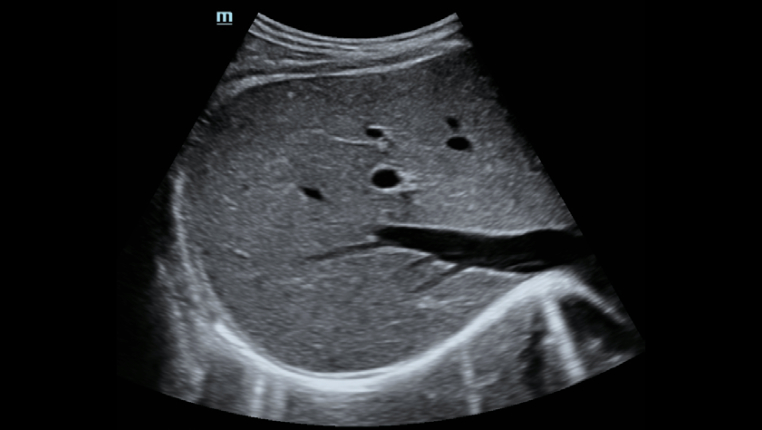

â Pun??o guiada por ultrassom dedicado para aprimorar a precis?o das biÃģpsias

â Pun??o guiada por ultrassom dedicado para aprimorar a precis?o das biÃģpsias